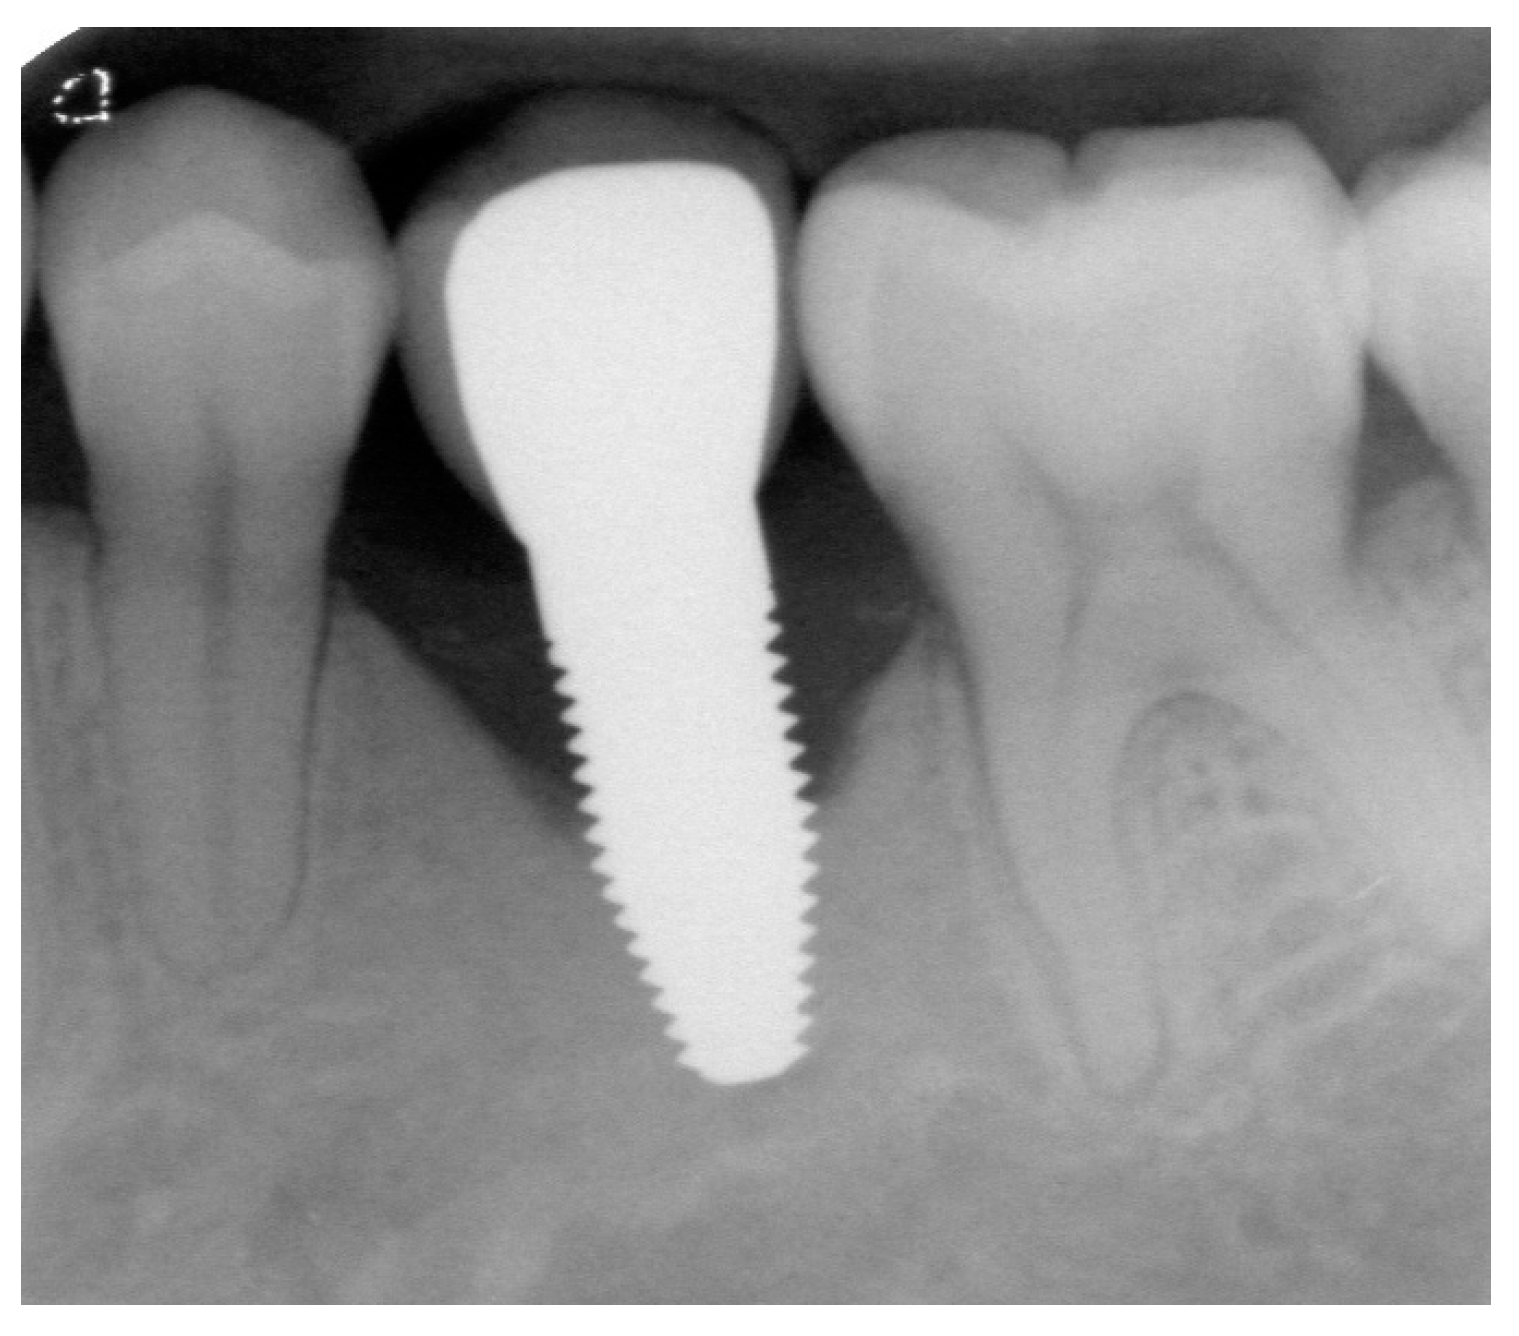

Appendix A. Exemplary Photographs and Radiographs from a Patient at Different Examination Time Points and a Positive Outcome